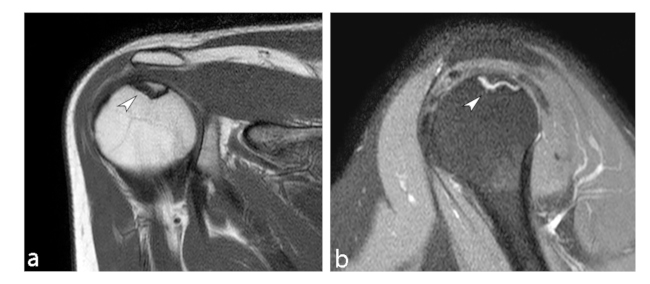

La ON de la cabeza humeral conocida como enfermedad de Hass es la segunda en frecuencia, se desarrolla en la región subcondral, puede provocar colapso del hueso subcondral necrótico, desarrollo de una superficie articular irregular y posterior degeneración de la articulación.

Puede tener varias etiologías: idiopática, secundaria a causas médicas (por fijación quirúrgica o artroscopia), farmacológica o secundaria a un trauma, siendo ésta última la más frecuente. Las fracturas de la cabeza humeral con tres fragmentos pueden desarrollar ON en 3 a 14% de incidencia, mientras que aquellas con cuatro fragmentos, entre 13 y 34%.19

Existe una escala para determinar el grado de severidad de la necrosis mediante hallazgos imagenológicos por RM con el fin de identificar y guiar el tratamiento adecuado, siendo esta la clasificación de Cruess Modificado (►Tabla 4) a partir de la clasificación Ficat y Arlet (►Figs. 9 y 10).20

Hertel describe criterios radiográficos como predictores de isquemia para establecer el compromiso vascular de la cabeza humeral: extensión metafisaria de la cabeza humeral de < 8mm y la disrupción del eje medial > 2mm. Estos hallazgos, en asociación a una fractura del cuello anatómico, presentaron un valor positivo predictivo de 97% para el desarrollo de isquemia.19